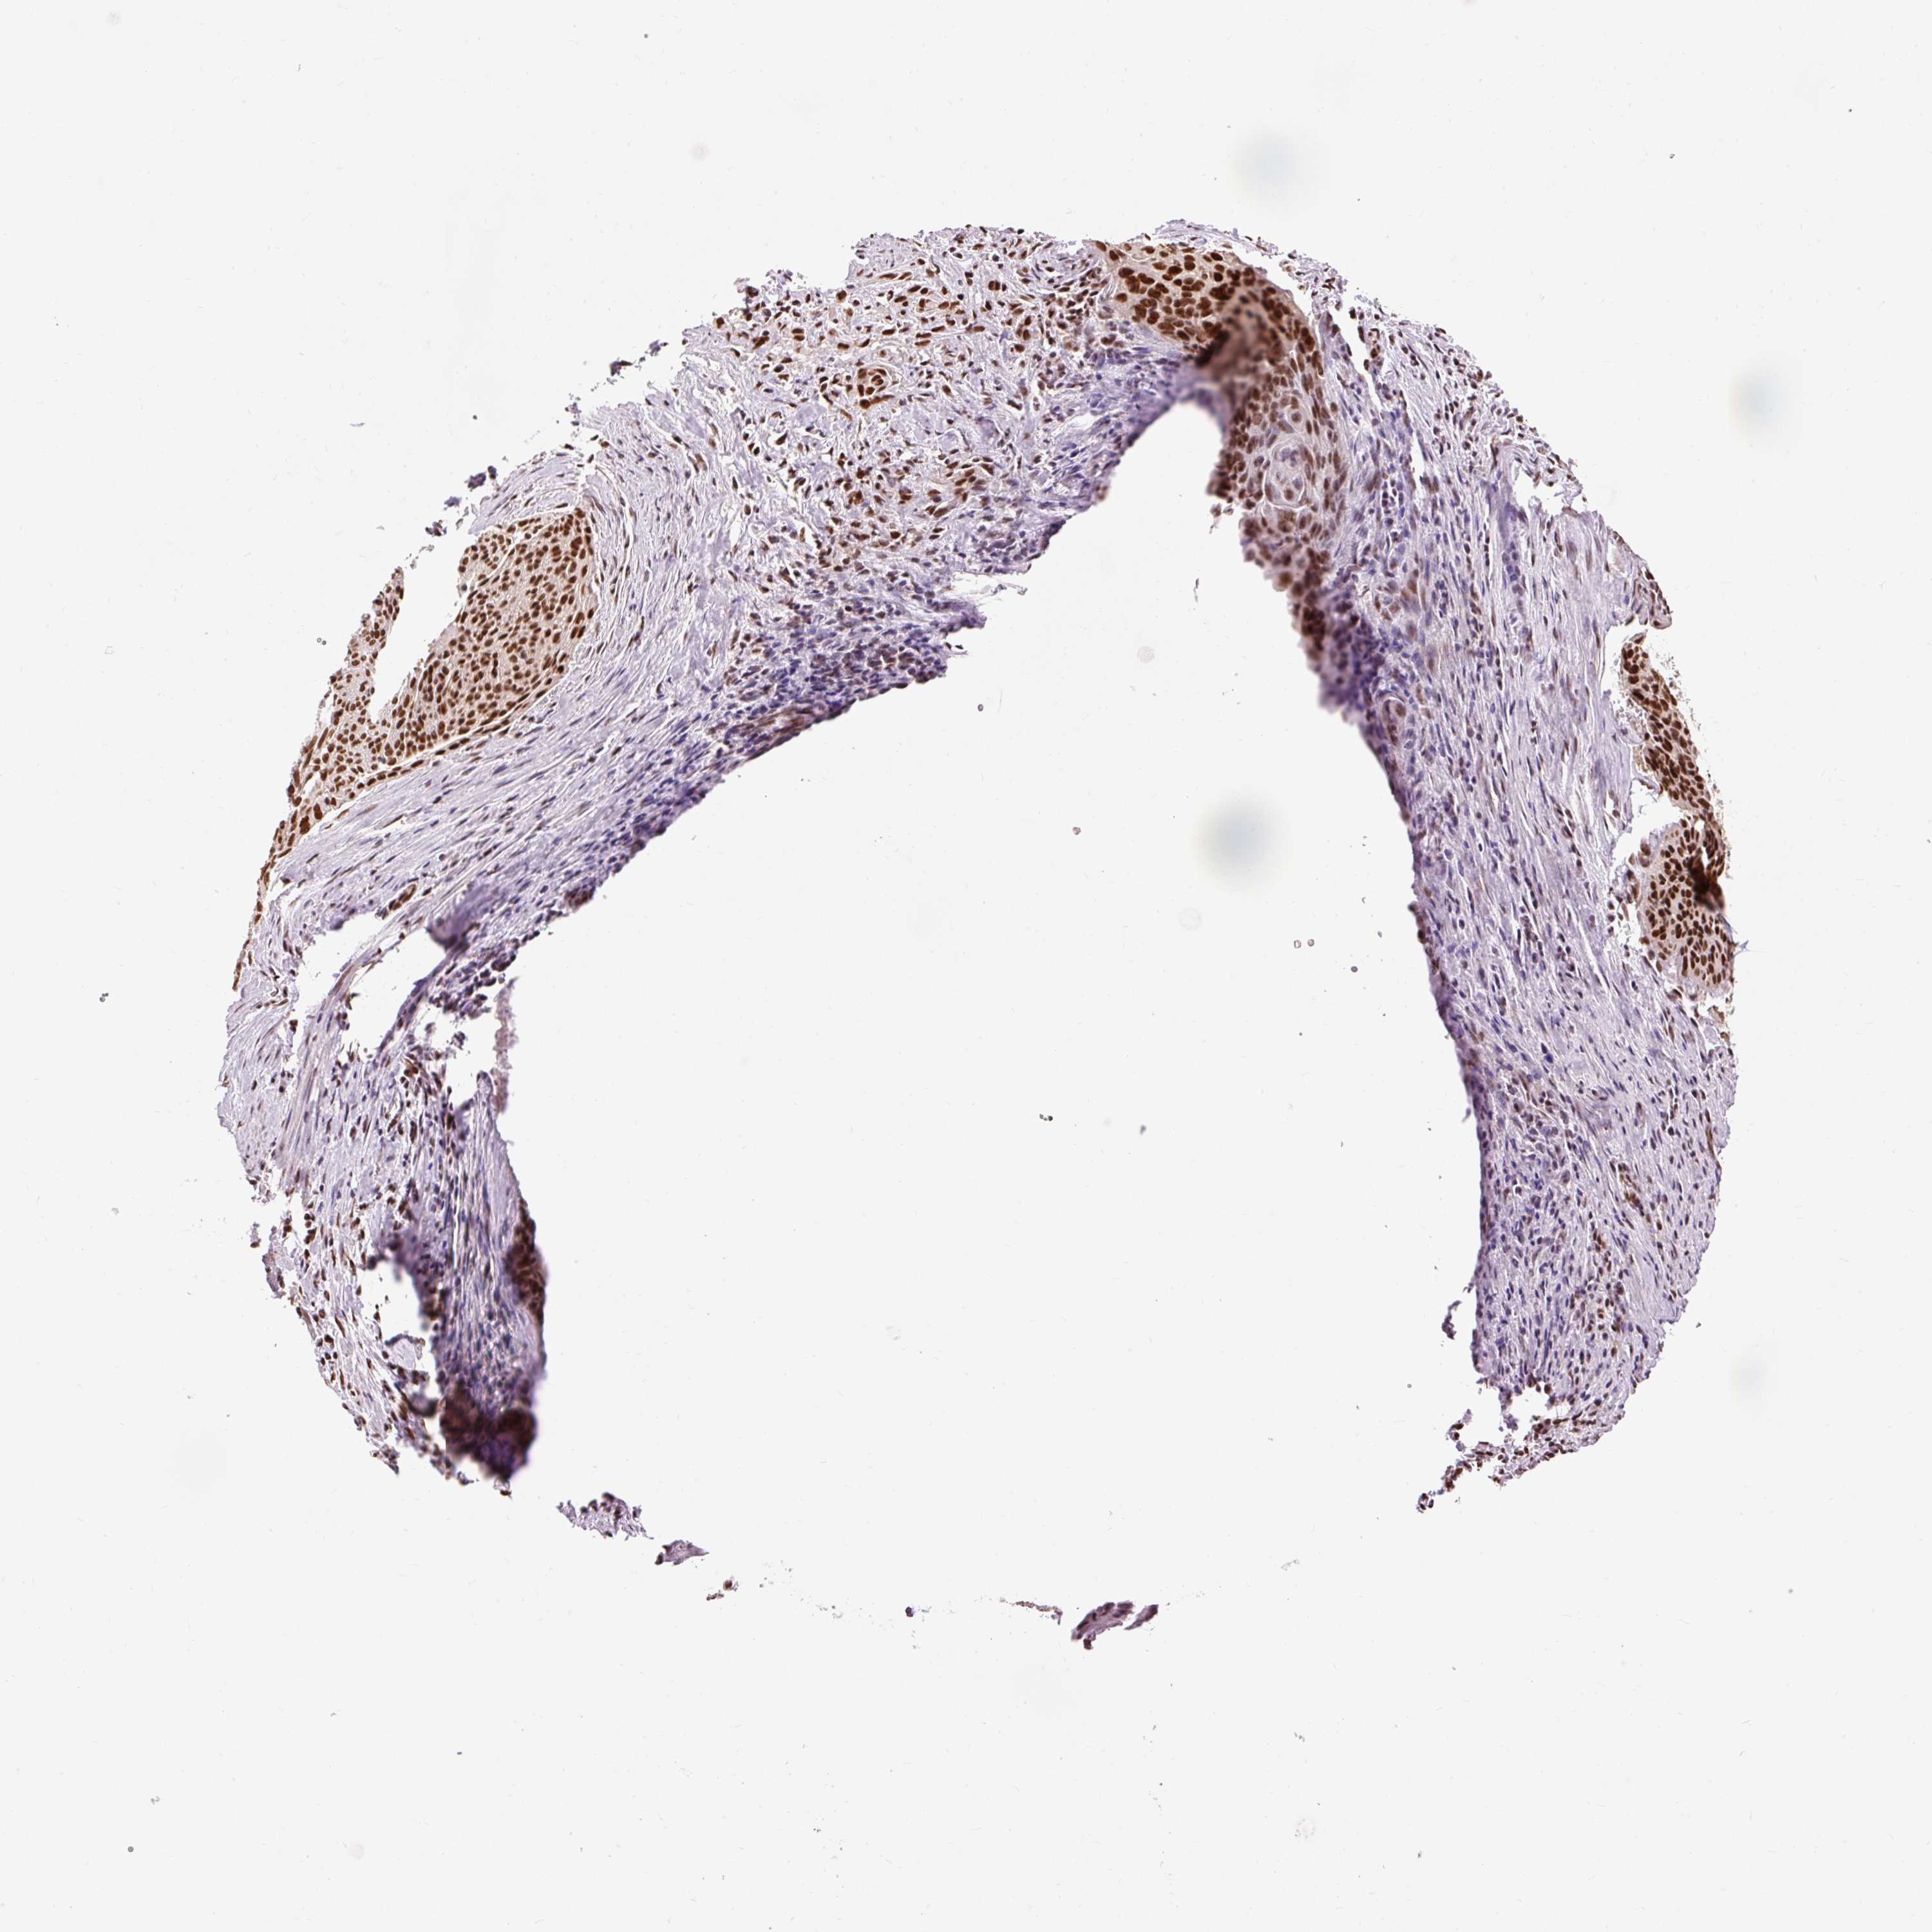

CERVICAL CANCER - Protein expressioni

A mouse-over function shows sample information and annotation data. Click on an image to view it in a full screen mode. Samples can be filtered based on level of antibody staining by selecting one or several of the following categories: high, medium, low and not detected. The assay and annotation is described here.

Note that samples used for immunohistochemistry by the Human Protein Atlas do not correspond to samples in the TCGA dataset.

Antibody stainingi

Antibody staining in the annotated cell types in the current human tissue is reported as not detected, low, medium, or high, based on conventional immunohistochemistry profiling in selected tissues. This score is based on the combination of the staining intensity and fraction of stained cells.

Each image is clickable and will lead to virtual microscopy that enables deeper exploration of all samples and also displays staining intensity scores, fraction scores and subcellular localization as well as patient and tissue information for each sample.

Antibody HPA052589

Staining

High

Medium

Low

Not detected

Intensity

Strong

Moderate

Weak

Negative

Quantity

>75%

75%-25%

<25%

None

Location

Nuclear

Cytoplasmic/membranous

Cytoplasmic/membranous,nuclear

Squamous cell carcinoma, NOS

Adenocarcinoma, NOS